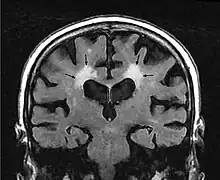

Leukoaraiosis is a particular abnormal change in appearance of white matter near the lateral ventricles. It is often seen in aged individuals, but sometimes in young adults.[1][2] On MRI, leukoaraiosis changes appear as white matter hyperintensities (WMHs) in T2 FLAIR images.[3][4] On CT scans, leukoaraiosis appears as hypodense periventricular white-matter lesions.[5]

These white matter changes are also commonly referred to as periventricular white matter disease, or white matter hyperintensities (WMH), due to their bright white appearance on T2 MRI scans. Many patients can have leukoaraiosis without any associated clinical abnormality. However, underlying vascular mechanisms are suspected to be the cause of the imaging findings. Hypertension, smoking, diabetes,[3] hyperhomocysteinemia, and heart diseases are all risk factors for leukoaraiosis.